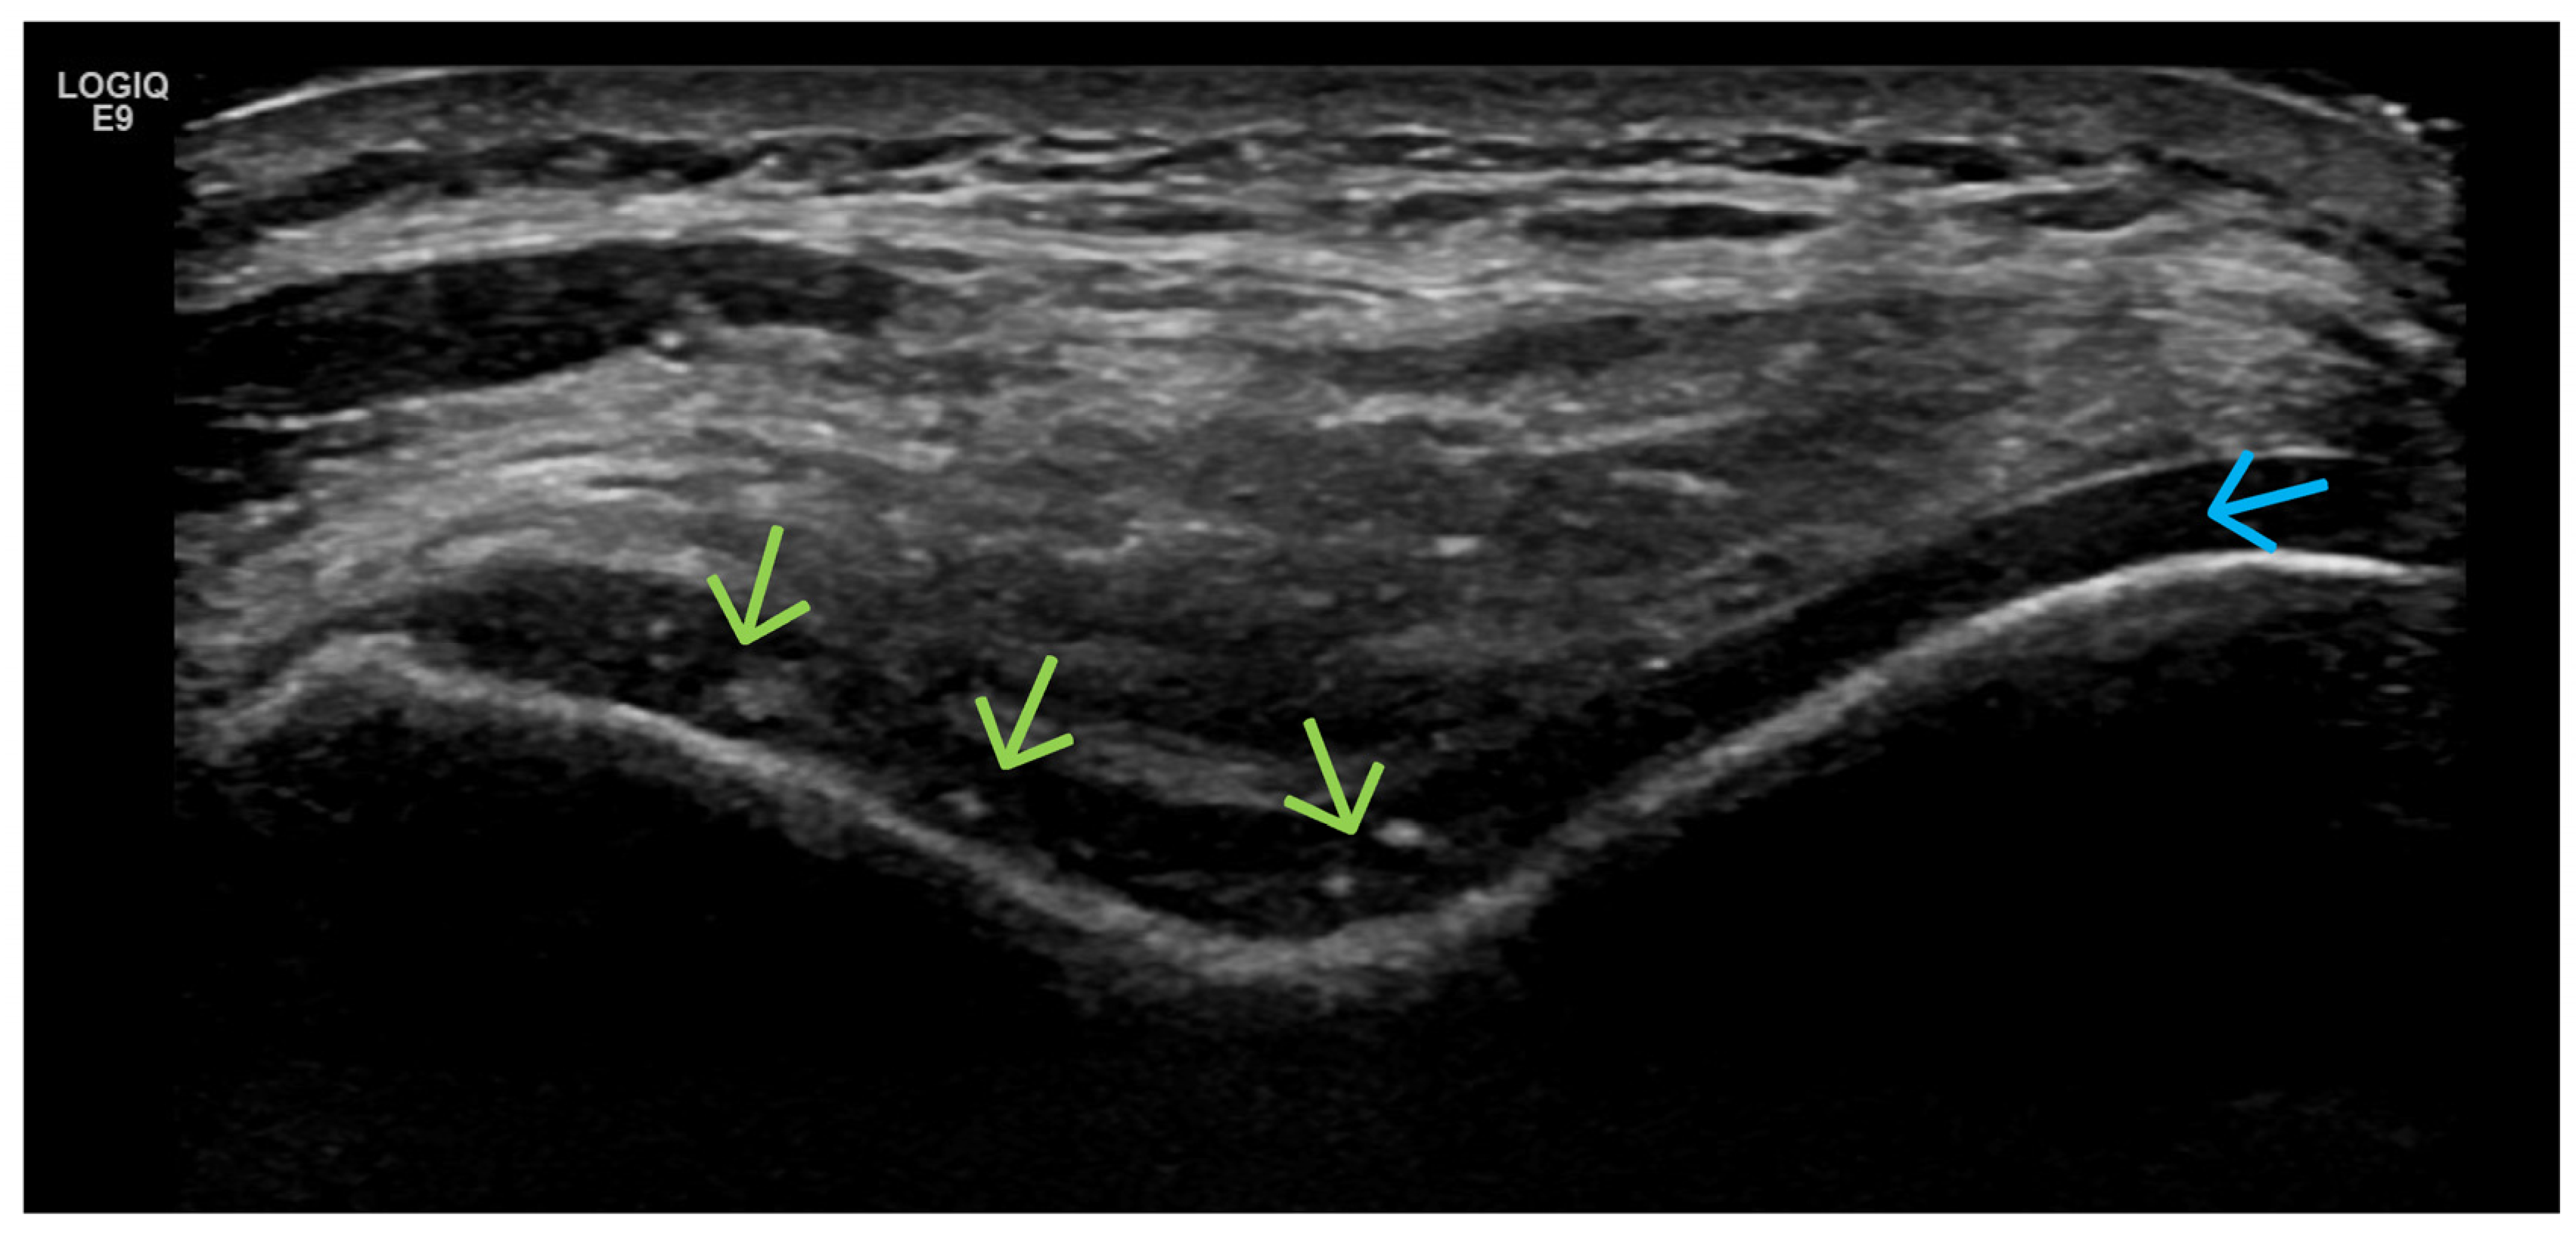

- Predominant cartilage destruction (with almost no synovitis and intra-articular effusion);

- Altered subchondral bone (superficial bone erosions or osteophytes);

- Crystal deposits (MSU, CPPD);